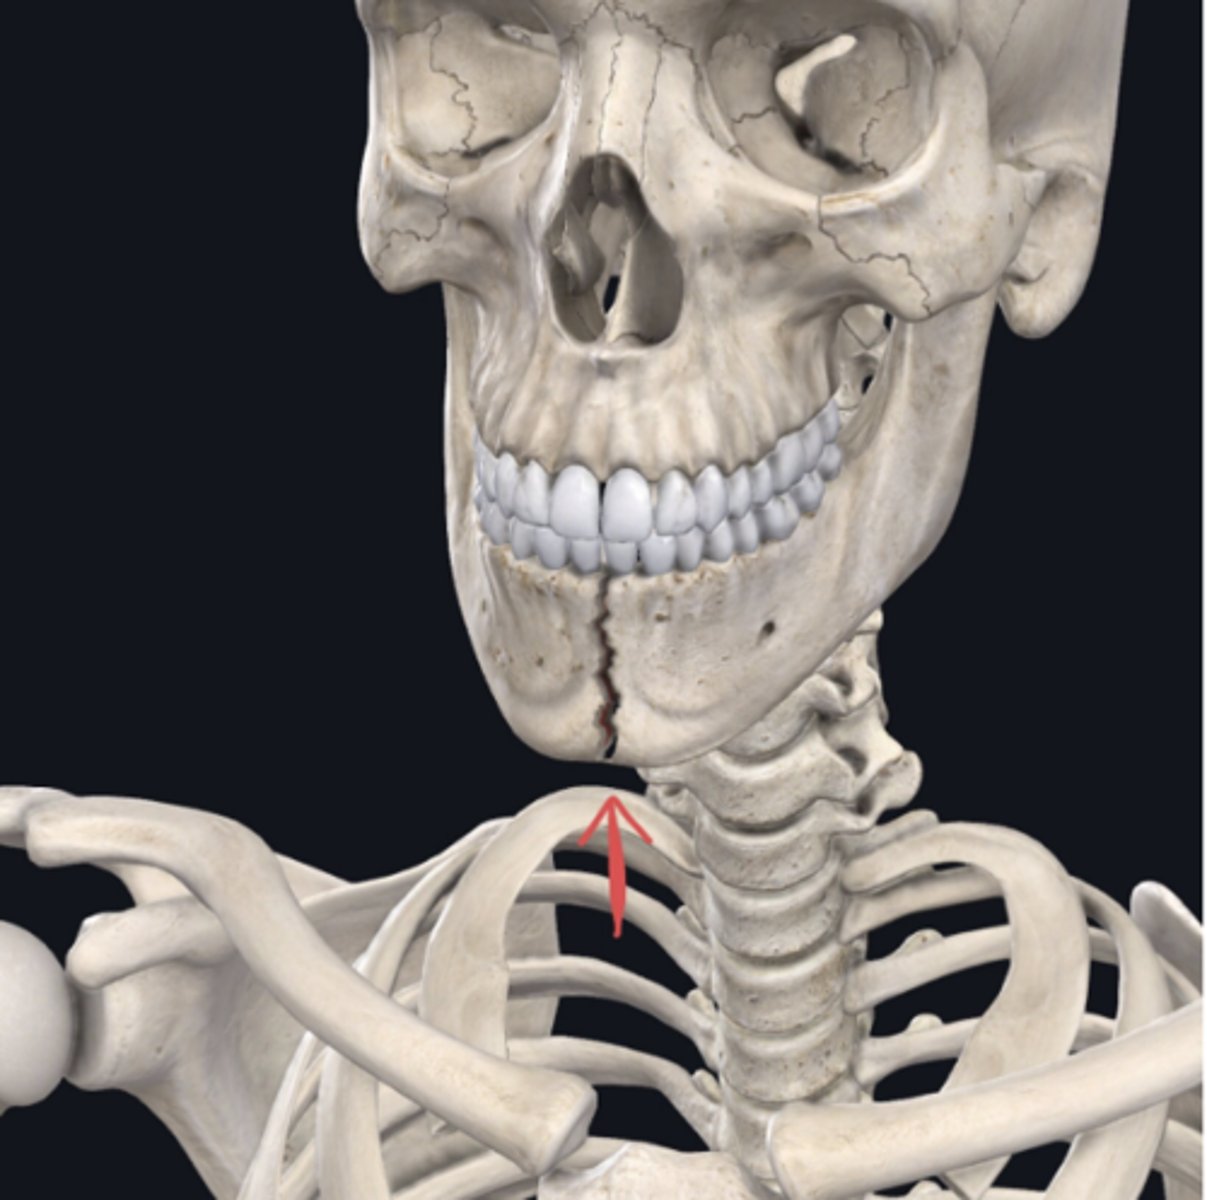

Identify the plane of section in which the indicated fracture has occurred. (Free response)

Frontal (coronal also correct)